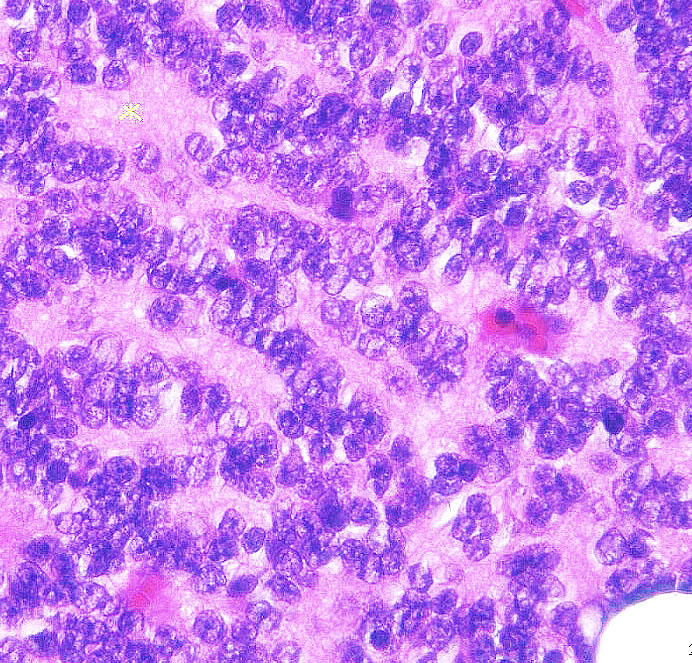

中間型松果体実質腫瘍 PPTID の病理

Sheets or large lobules of uniform cells with moderate nulear atypia and low to moderate mitotic activity, transitions from rosette-bearing areas to diffuse, sheetlike growth, 2 > mitoses (10HPFs), 3-10% MIB-1.

松果体芽腫と松果体細胞腫の中間に位置する病理像です。松果体細胞腫より細胞密度が高く,軽度から中等度の核異型があり,分裂能が中等度に高いとされます。左の写真のように,松果体細胞腫に似たrosetteを作りながらも細胞密度が高くびまん性に細胞核が集積する部分も見られたり,右の写真のように「ごく一部」に巨細胞が見られたり核異型を伴う細胞が出現します。Homer Wright rosetteやganglion cellの出現もあります。グレード2とグレード3を分ける基準ははっきりしていませんが,分裂能を基準にすることが多いです。MIB-1が 3 to 10%すから,8%くらいだとグレード3となるかもしれません。また腫瘍の大部分が松果体細胞腫の所見で,一部に上記のような所見のあるものはグレード2とします。注意しなければならないのは,グレード2と3の定義は非常にfazzyであることです。これによって局所照射か脳脊髄照射を選択することはとても危険なのですが (・・?)